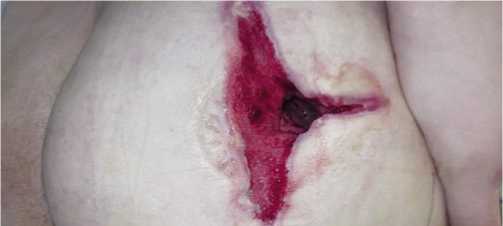

Скрининговая и первоначальная классификация ран осуществлялась наиболее простым и вместе с тем удобным методом – разделение по их цвету [12]. Внешний вид хронической раны, описанный и фотодокумен-тированный по цветовой гамме, позволяет достаточно достоверно определять стадию раневого процесса, оценить его динамику, разработать программу местного лечения раны до получения результатов бактериологических исследований и применения комплекса инструментальных исследований (компьютерная томография, рентген, УЗИ, допплерография, ангиография и т.д.). Раны черного (Рис. 1) и темного (Рис. 2) цветов соответствовали I стадии раневого процесса, однако в первом случае обычно имеется сухой некроз, а во втором – влажный. Наличие красной (Рис. 3) раны свидетельствует о переходе раневого процесса во II стадию регенерации. Белая (Рис. 4) рана определяется при эпителизации раневого дефекта, что соответствует III фазе течения раневого процесса.

Рис. 3. Хроническая рана красного цвета после огнестрельного ранения.

Рис. 4. Хроническая рана белого цвета после вскрытия флегмоны с эпи-телизацией раневого дефекта.